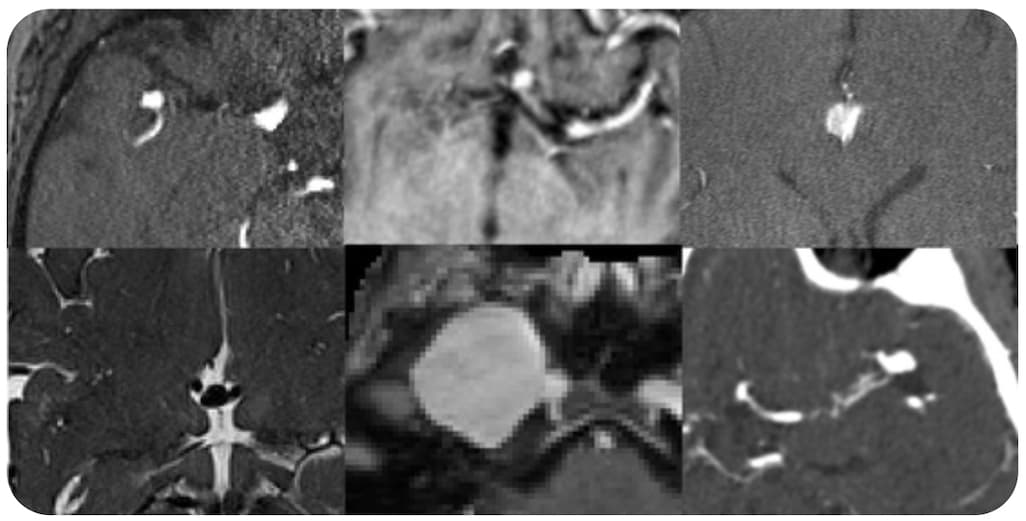

La tomodensitométrie quantitative serait une bonne alternative à l’ostéodensitométrie pour le dépistage de la fracture par déminéralisation osseuse. Pour gagner en précision dans l’évaluation de la DMO par TDM, une étude introduit le deep learning afin de définir une norme d’atténuation trabéculaire...